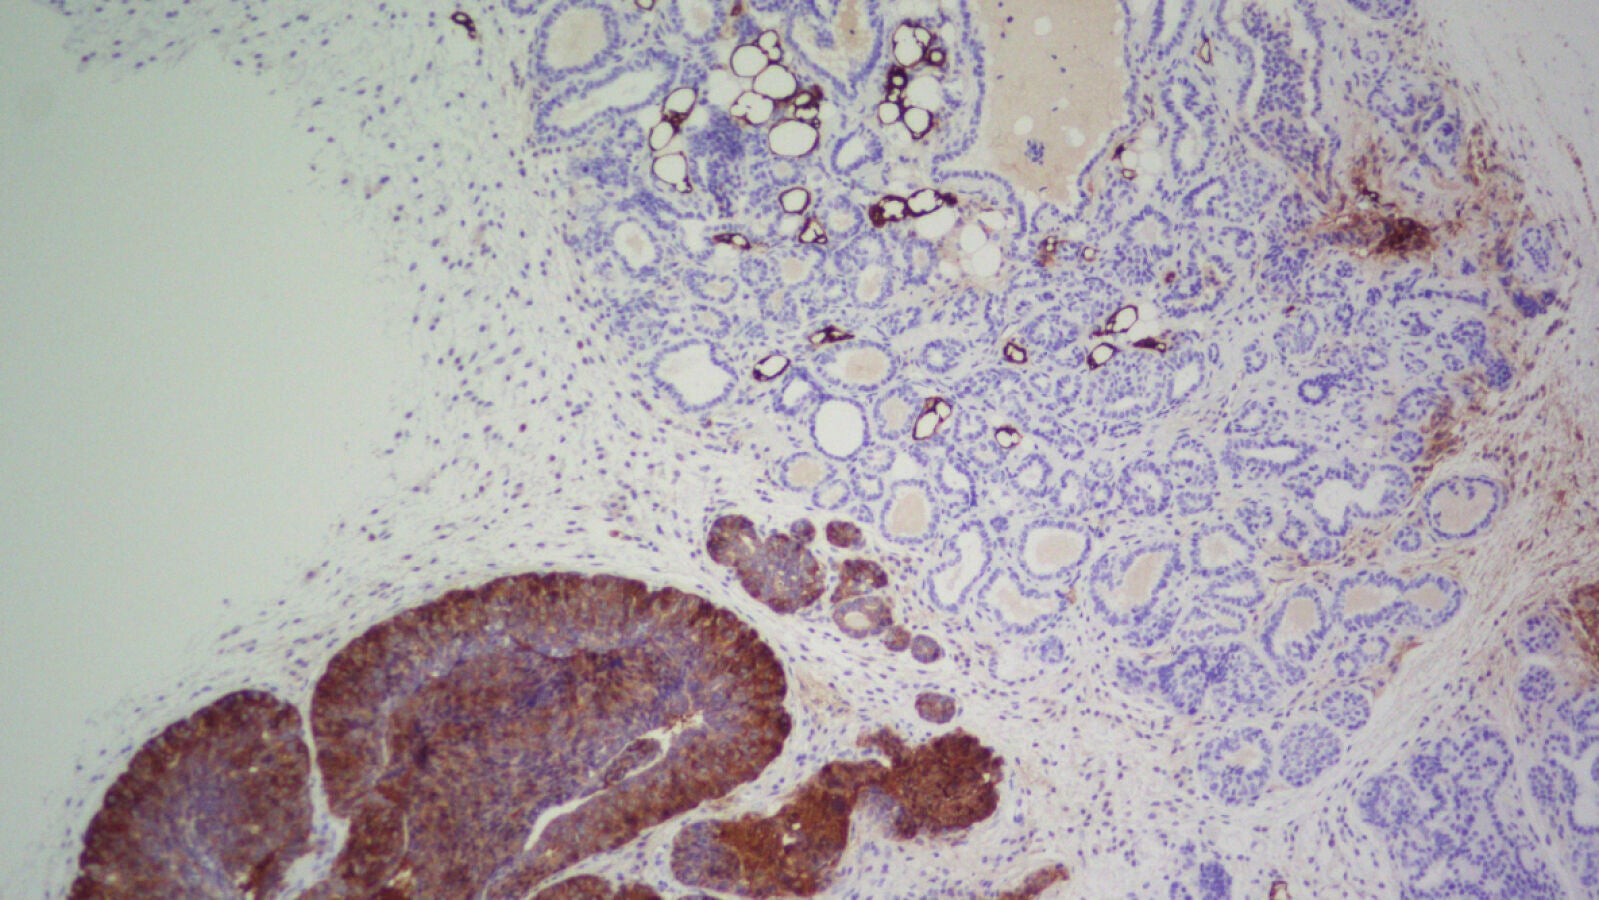

Trabajando con un modelo transgénico de ratón que desarrolla un tipo agresivo de cáncer de mama, el equipo comprobó que al eliminar FASN los tumores no aparecían. Quintela indica por qué: “El crecimiento independiente del anclaje aumenta la cantidad de radicales libres que producen las mitocondrias, lo que, llegado a un punto de acumulación, asfixiaría a las células del cáncer y estas morirían”.

“Lo evitan utilizando FASN, ya que regula un proceso llamado carboxilación reductiva que elimina este exceso de radicales libres. Por ello, cuando bloqueamos FASN en nuestro trabajo, los radicales libres se acumularon sin freno, lo que impidió que se produjera el crecimiento malignizado”, subraya.

“En nuestro modelo de ratón que desarrolla un cáncer de mama muy penetrante, las zonas en las que hay FASN sí desarrollan cáncer, mientras que en las zonas donde lo bloqueamos no llegaron a generarse tumores y la supervivencia aumentó en un 68 %”, dice Quintela. “Pero cuando tratamos de inhibir FASN con los tumores ya establecidos, hubo un pequeño efecto transitorio que casi no afectó a la progresión”.